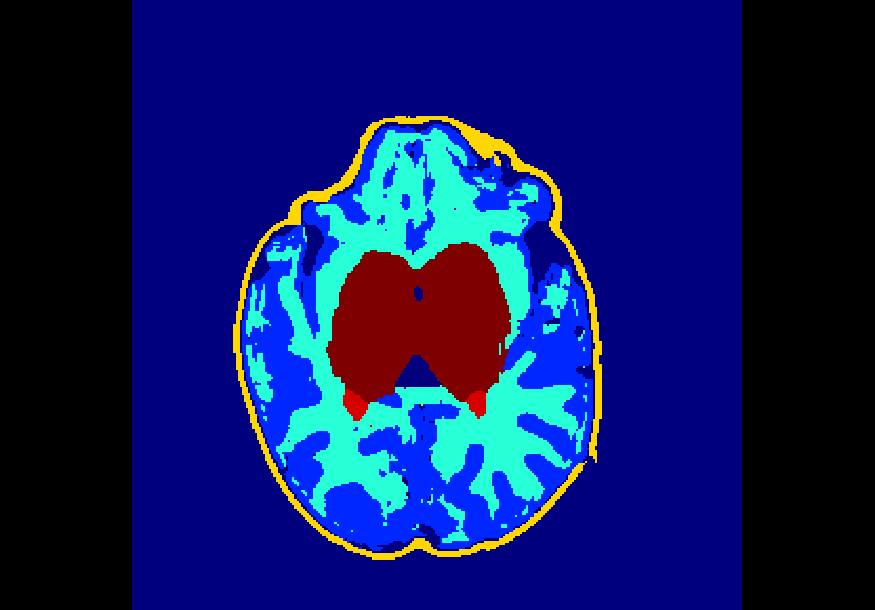

The dataset consisted of 70 3D T2-weighted brain MRI scans publicly available from the dHCP neonatal cohort. The segmentation maps had 10 classes, corresponding to: zero-pixel background, cerebrospinal fluid (CSF), cortical grey matter (cGM), white matter (WM), background bordering brain tissues, ventricles, cerebellum, deep grey matter (dGM), brainstem, and hippocampus. The scans covered an age range of 24.3-42.2 weeks. The data was available in NIfTI format; Figure 1 shows an example scan and corresponding tissue labels. We carried out a pre-processing step where each scan was independently normalised to zero-mean and unit-variance.

Finally, Table 4 shows that the model trained on data injected with different degrees of both Gaussian and salt-and-pepper noise (gaus01, gaus03, gaus04 with = 1, 3, 4 ; snp01, snp05, snp10 with prob = 0.01, 0.05, 0.10) achieves the best overall robustness across the 16 versions of the test set, where even the heaviest filtered images had very few segmentation inaccuracies. For instance, this model demonstrated high levels of robustness on all 10 classes for noise-free data, on data injected with a previously unseen degree of salt-and-pepper noise (e.g. DSCs of 88%-99% on snp20), as well as on data with a previously unseen degree of Gaussian noise (e.g. DSCs of 72%-98% on gaus05). To illustrate, Figure 5 shows examples of the predicted segmentation of the model on the heaviest transformed images of the three filter categories used in these experiments. From the figure it is clear that the model achieved excellent mapping of the brain tissue regions. This shows a tremendous improvement from the baseline model which was trained using a conventional, noise-free approach and thus failed severely on the heavily corrupted images (e.g. DSCs of 0% for all 10 classes on snp20, see Table 2).